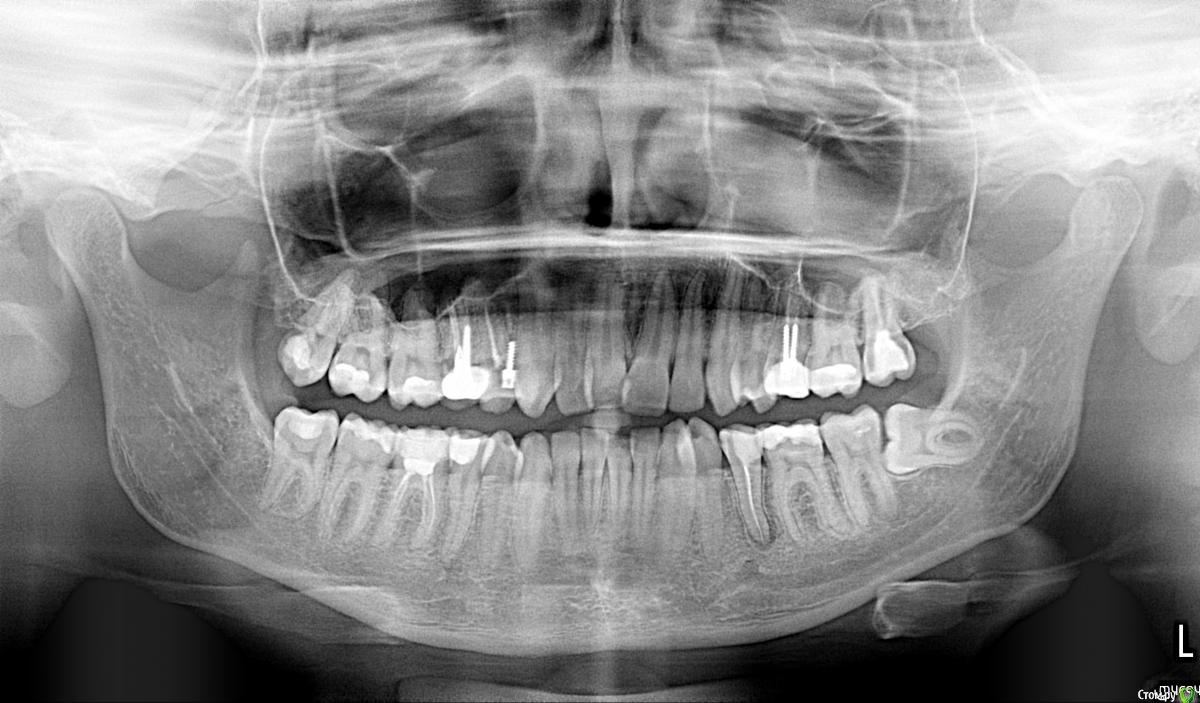

aqua1 Опубликовано 8 февраля, 2015 Поделиться Опубликовано 8 февраля, 2015 Добрый день! История моя давняя и до сих пор не решена….Где-то в 2007 году удалили в нижней 5-ке нерв, но зуб иногда «простреливал» при случайном накусывании по ночам. Подозреваю, что неудачное лечение могло быть связано с тем, что немного передержали лекарство, так как врач был в отпуске..Через полгода, в 2008 году на десне между 5 и 6 образовался бугорок, снимок показал воспаление на корне. Так как каналы на снимке были запломбированы хорошо, сказали что нет смысла их перелечивать, и зуб придётся удалить(( Естественно, меня такой поворот не устраивал, зуб был хорошо сохранен, никогда не беспокоил, и лечение кариеса изначально было просто профилактическим, но канал оказался слишком близко... Второй вариант был антибиотики, образовался свищ, а вскоре всё зажило и припухлость полностью спала (хотя на снимке 2009 года ситуация не изменилась).Ни зуб, ни дёсны не беспокоили меня абсолютно до весны 2012 года, когда после ветреной погоды, зуб поныл 2 дня и образовалась даже не припухлость, а затвердевшая дуга вдоль 6-8 зубов. Боли и воспаления не было. Испугавшись, что это будет расти и дальше такими же темпами, поехала в стоматологию, где терапевт отправила меня к хирургу, у которого было 2 варианта – резать или вырывать. На новом снимке никаких изменений опять замечено не было.. Десну разрезали между 5 и 6, гноя не было, потом отёк сошёл, а затвердение нет.В настоящий момент оно особо не беспокоит, только иногда ощущается в челюсти, асимметрии лица тоже вроде не заметно. В 2014 году начала активно лезть полулежачая восьмерка, без боли и воспаления. Затвердевшая дуга на десне начинается под 6-м зубом и плавно уходит за эту 8-ку. По случаю всего этого в январе 2015 сделали панорамный снимок всей этой красоты.Очень нужны ваши советы!1) Обязательно ли удалять эту 5-ку или как её лечить? Сойдет ли затвердение на десне после удаления? Что это вообще может быть?2) Я так понимаю, что 8-ка на удаление. Стоит ли немного подождать, пока она вылезет побольше, чтобы легче её удалить?Заранее спасибо. Прилагаю всю историю в рентгенах, а также фото, как это выглядит сейчас вживую. Ссылка на комментарий

aqua1 Опубликовано 8 февраля, 2015 Автор Поделиться Опубликовано 8 февраля, 2015 (изменено) Разъяснения по снимкам:1) весна 2008 года - начало2) 2009 год3) весна 2012 года - сразу после обострения и появления отвердевшей десны4) свежий снимок 2015 года5) так выглядит зуб мудрости4) зубы и десна в обычном состоянии7) и 8) - изображения отвердевшей дуги на десне вдоль 6, 7 и 8 зубов (т.е. та область, что между зубами и пальцем) Изменено 8 февраля, 2015 пользователем aqua1 Ссылка на комментарий